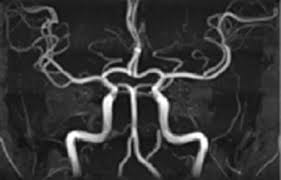

- MRA (자기공명혈관조영술): MRI 원리를 적용해 **혈관 내부 구조와 혈류 흐름**을 3D 영상으로 확인하는 검사입니다. 동맥류, 혈관 협착·폐쇄·혈전 등의 진단에 사용됩니다 :contentReference[oaicite:2]{index=2}.

즉, MRI는 **조직 중심** 진단, MRA는 **혈관 상태와 혈류 흐름**을 중점으로 합니다 :contentReference[oaicite:3]{index=3}.